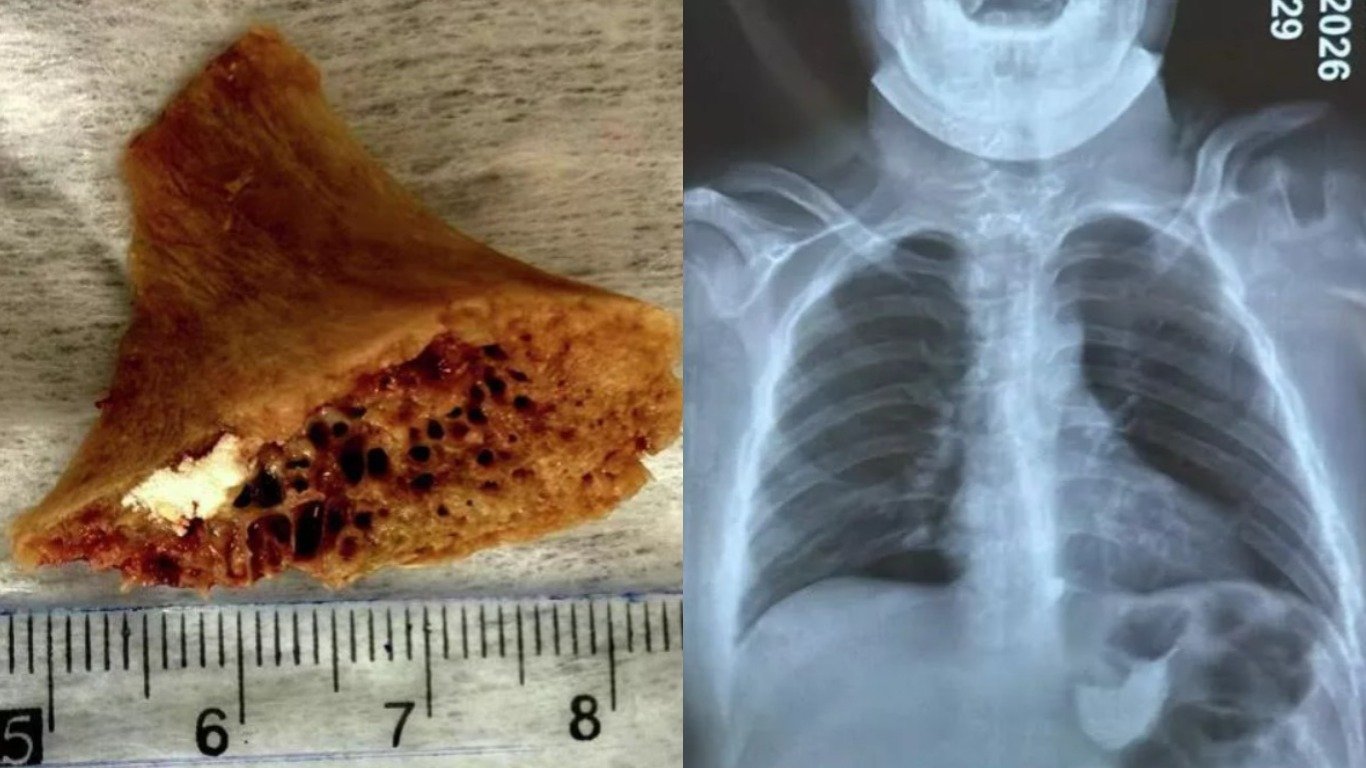

В Бишкеке 15-летний подросток проглотил кость, которая застряла у него в пищеводе. Кость размером 3,5×4 см врачи удалили хирургическим путем. Об этом сообщила Городская детская клиническая больница скорой медицинской помощи Бишкека.

Врачи хирургического отделения этого учреждения провели операцию и извлекли застрявшую кость. Операция была выполнена с участием специалистов и профессоров. В настоящее время состояние подростка стабильное, его здоровье восстанавливается.